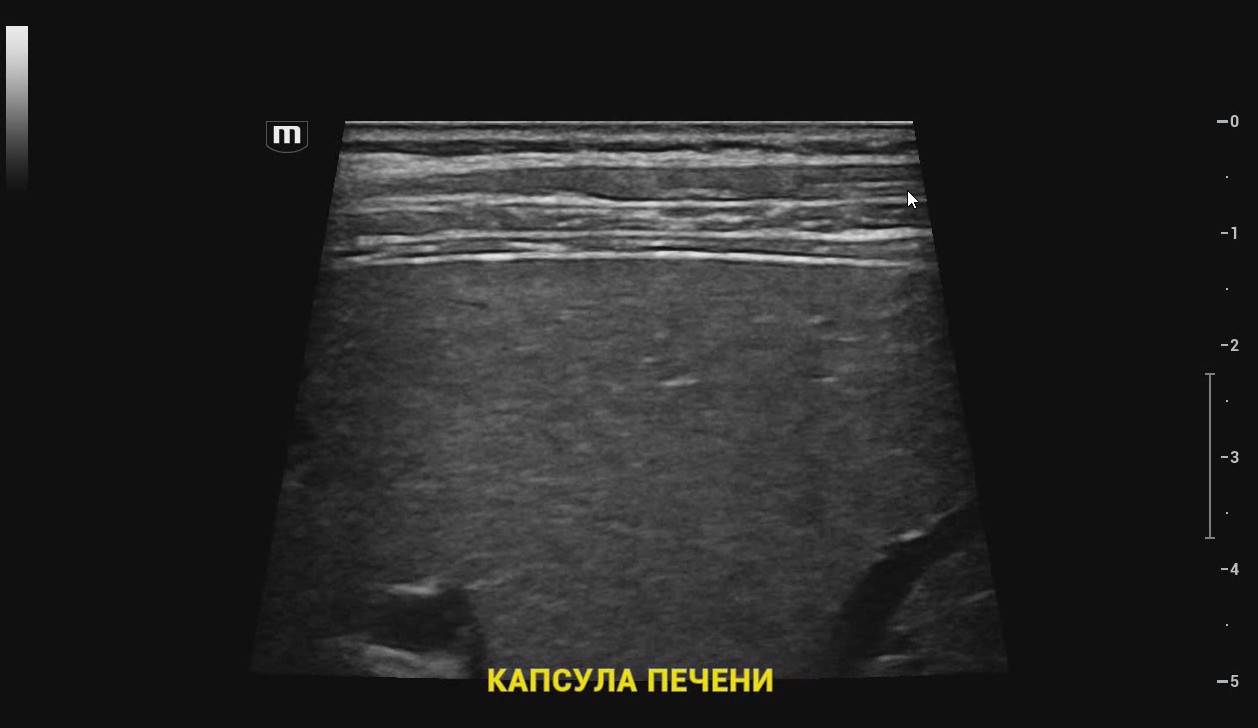

УЗИ аппарат Mindray Resona I9 – экспертный сканер в линейке производителя Mindray. Ультразвуковой аппарат поддерживает все современные технологии визуализации и протоколы расчетов для быстрого и точного проведения диагностики в разных областях медицины.

Платформа ZST+ Платформа ZST + — это уникальное инновационное решение, являющееся новой ступенью развития технологий в области ультразвуковой диагностики. В основе данной платформы - преобразование метода обработки ультразвуковых данных из традиционной в зонную, благодаря чему преодолевается традиционный компромисс между пространственным, временным разрешением и однородностью изображения ткани, что обеспечивает исключительное качество визуализации.